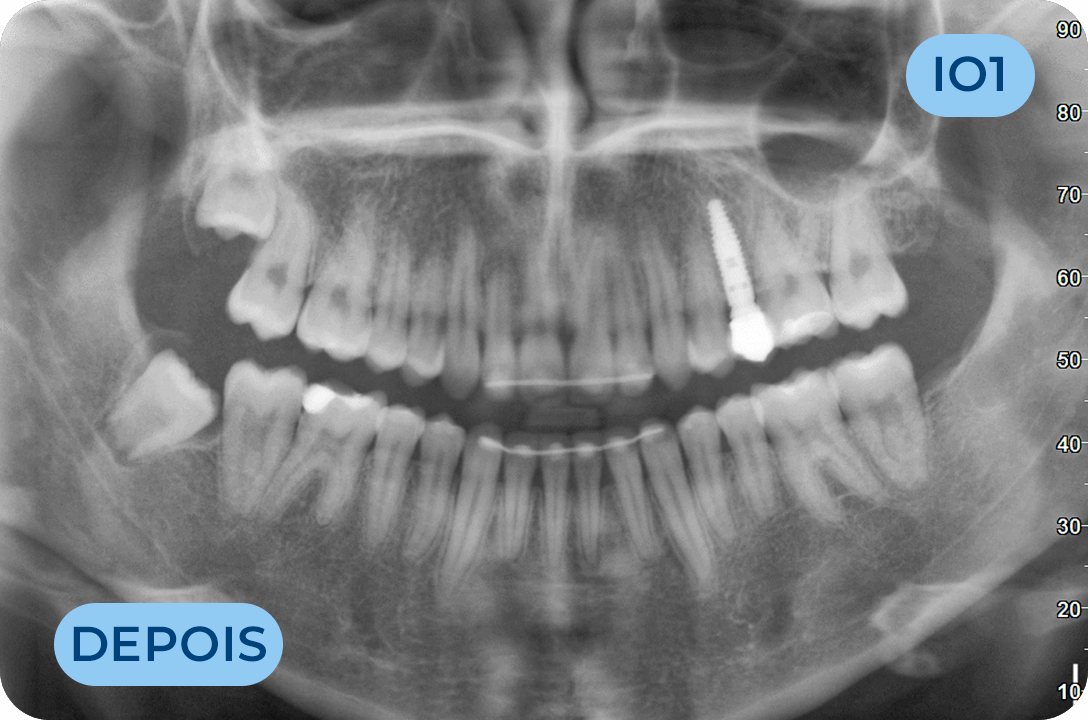

Implantologia Oral

É a área clínica que permite substituir os dentes ausentes através da colocação de implantes dentários. É uma solução definitiva, fixa e estética, que permite substituir apenas um dente, vários dentes ou todos os dentes.